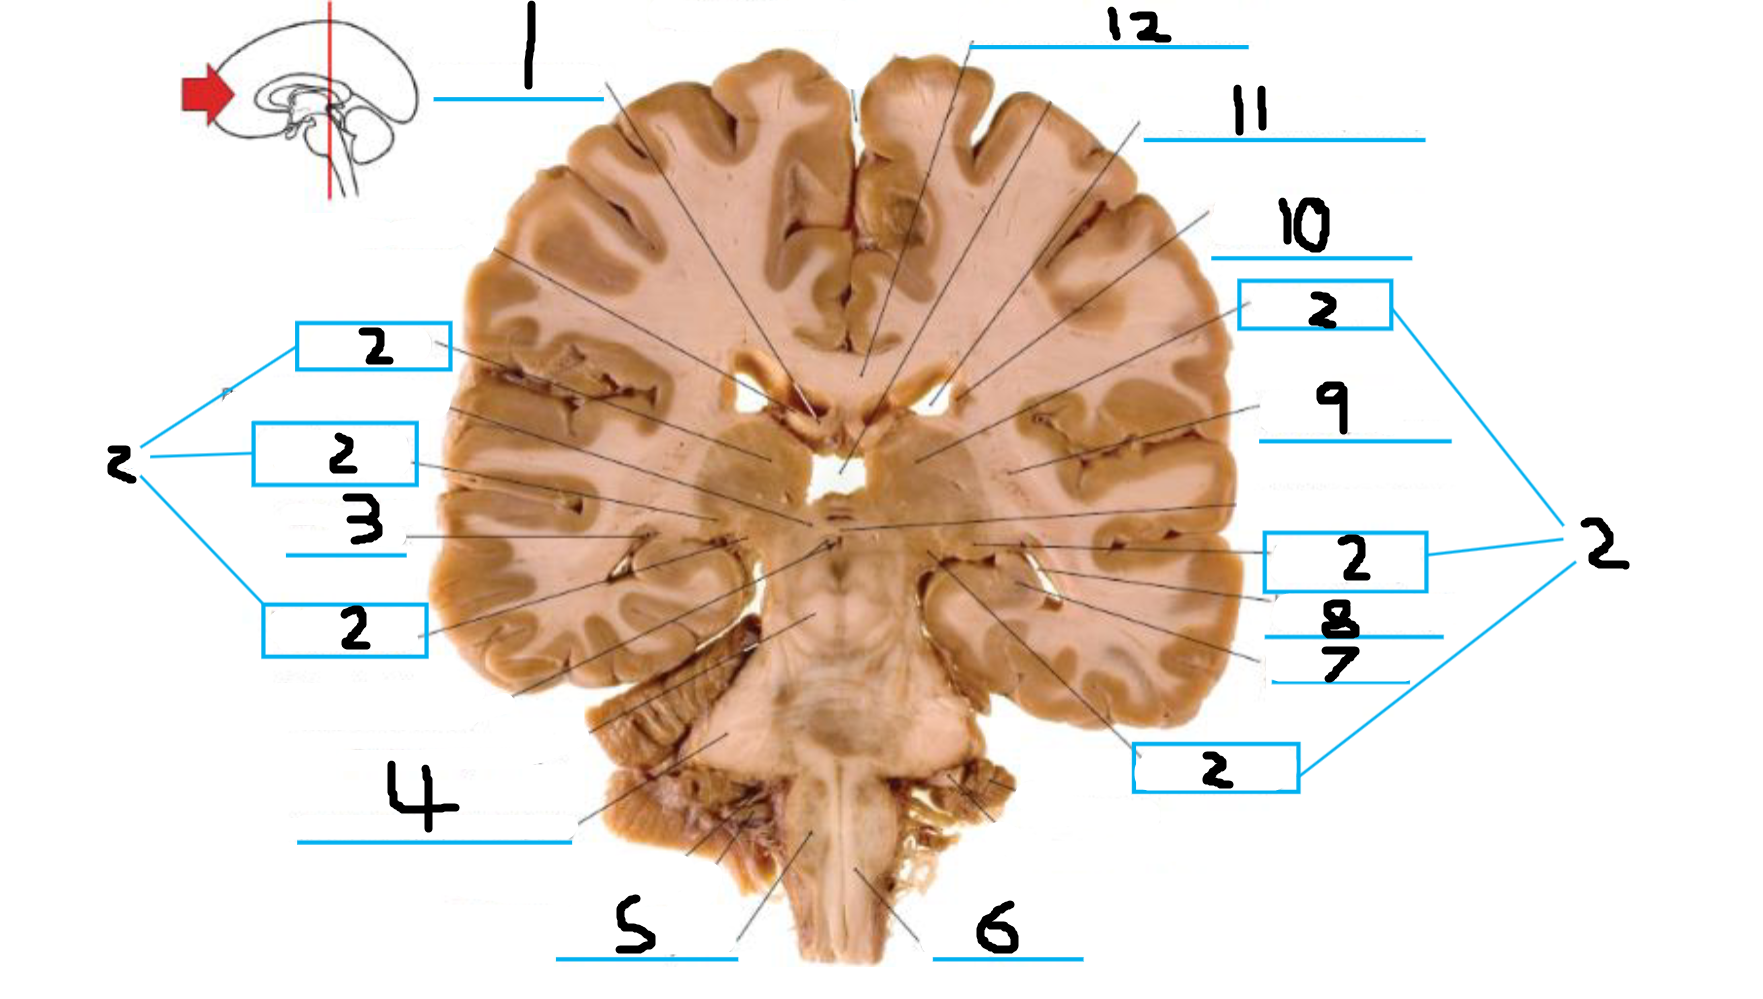

#1 is the:

Cingulate Gyrus

#2 is the:

Septum Pellucidum

#3 is the:

Lateral Ventricle

#4, #7, and #12 is the:

Fornix

#5 is the:

Third Ventricle

#6 is the:

Anterior Commissure

#8 and #11 is the:

Amygdala

#9 is the:

Hypothalamus

#10 is the:

Mammillary Body

#13 is the:

Insula

#14 is the:

Globus Pallidus

#15 is the:

Putamen

#16 is the:

Internal Capsule

#17 is the:

Caudate

#18 is the:

Corpus Callosum